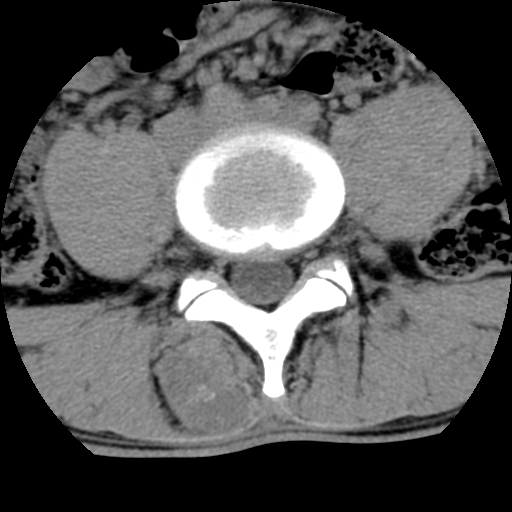

男,腰背痛

本人诊断1tb2包虫,请会诊

1)右侧竖脊肌稍低密度肿块伴钙化(性质待定),不排除肿瘤可能;建议行进一步检查。2)腰椎间盘突出。

1.右侧竖脊肌软组织肿块伴团块状钙化,首先考虑血管瘤可能性大;建议行进一步检查;2。腰椎间盘突出。